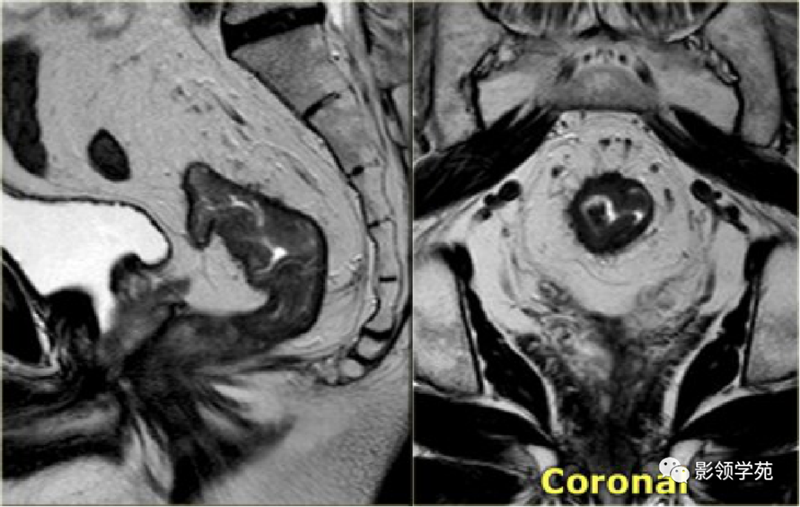

1、影像学检查:如X线胃肠道钡餐造影、CT检查、MRI检查、经直肠超声检查。腹部X线检查适用于伴发急性肠梗阻病人,可见梗阻部位上方的结肠有充气胀大现象。直肠癌术前行直肠MRI为常规检查项目,是术前分期的重要依据。

直肠癌磁共振影像